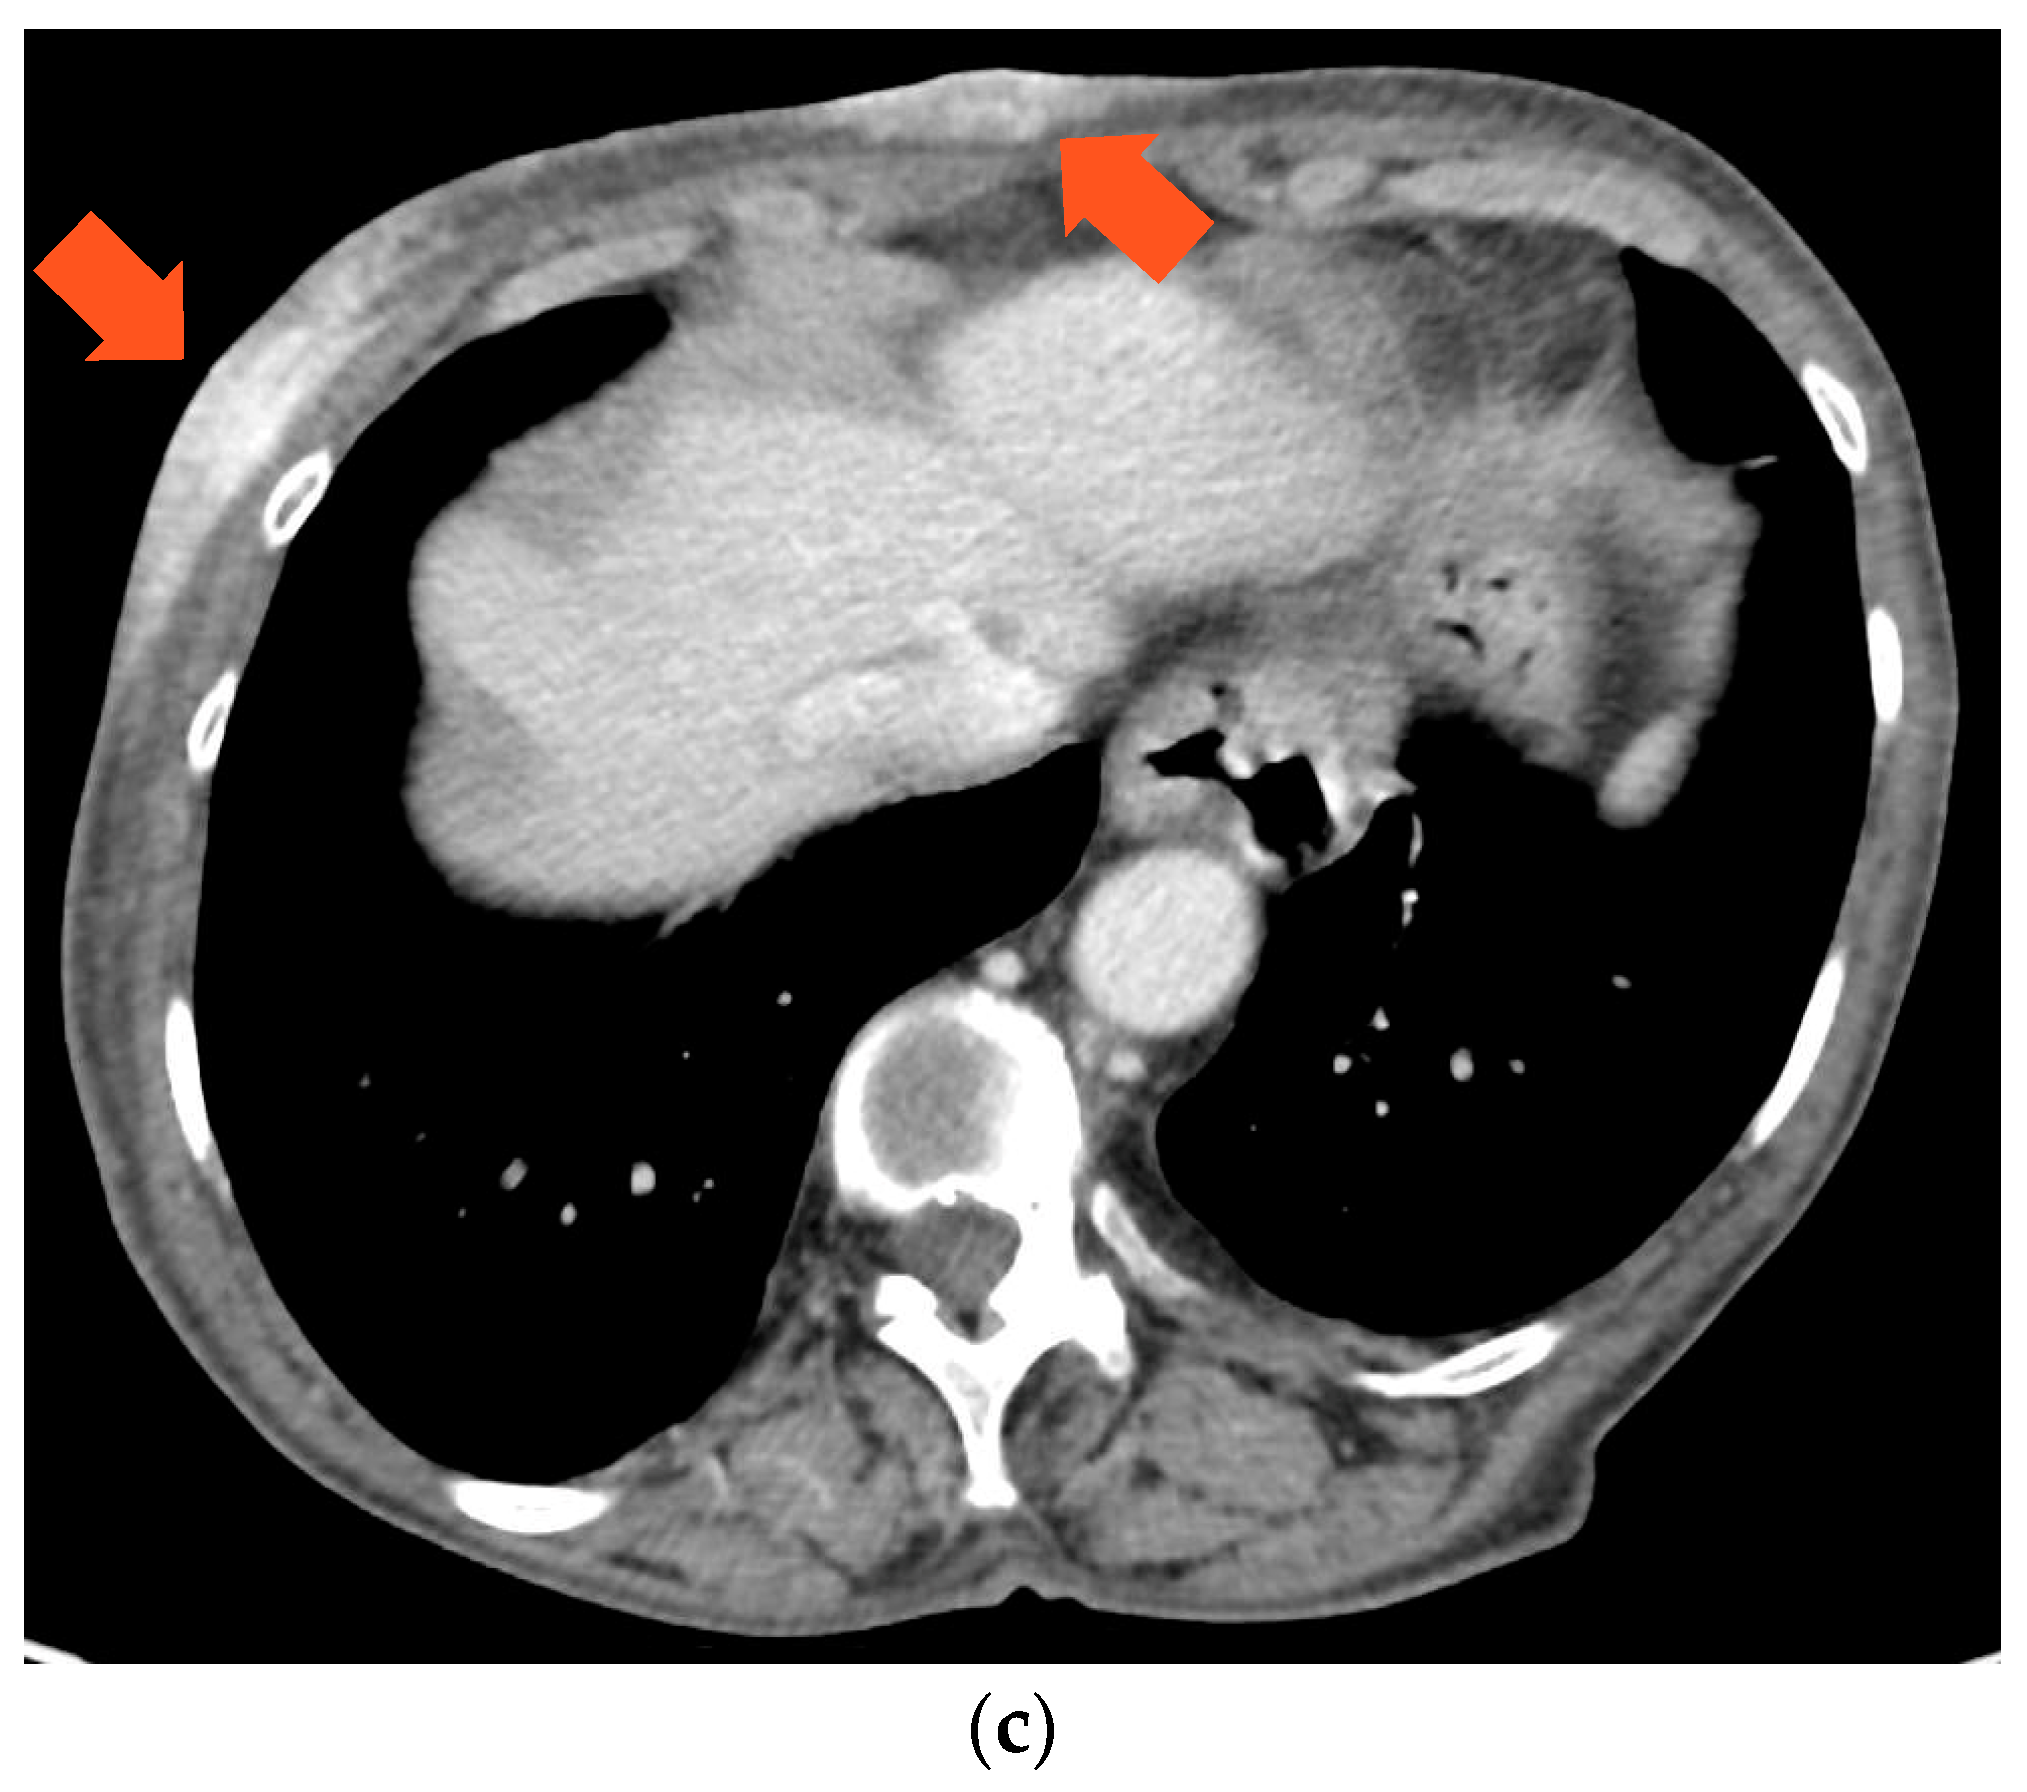

In February 2021, the patient returned to us due to the onset of multiple cutaneous erythematous nodules on the chest wall, which were consistent with a new recurrence of pleiomorphic lobular breast carcinoma, grade 3 (Figure 3). A core-needle biopsy revealed that the tumor had acquired endocrine sensitivity, with ER 70%, negative PgR expression, AR 70%, HER2 IHC 1+, and Ki67 10%. Carcinoembryonic antigen (CEA) and carbohydrate antigen 15.3 (CA15.3) were slightly elevated, namely 6.1 ng/mL (range 0–5) and 35.2 IU/mL (range 0–27), respectively. A total body contrast-enhanced computed tomography (CT) scan was performed, which excluded the presence of distant metastases (Figure 3C). Given the HR positivity, the patient started standard first-line therapy with the cyclin-dependent kinase 4/6 inhibitor (CDK4/6i) palbociclib and letrozole.

Figure 3.

(a,b) Chest wall recurrence and (c) tumor cutaneous infiltration at the CT scan.